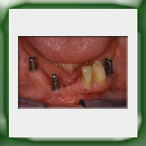

Circolare lega aurea e ceramica su impianti